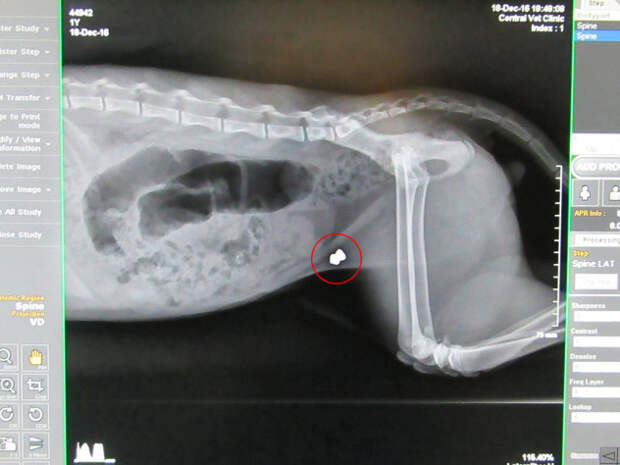

Исследования показали, что пуля все еще находится в задней части туловища кота. Крупное везение – немного дальше, и Санта либо погиб бы, либо остался парализованным, так как пуля могла разорвать позвоночник!